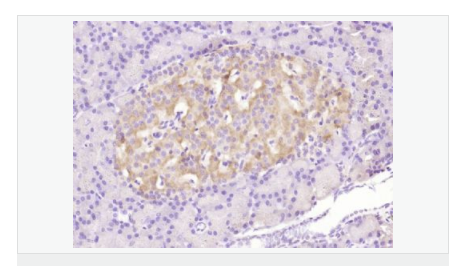

| 產品應用 | WB=1:500-2000 ELISA=1:5000-10000 IHC-P=1:100-500 Flow-Cyt=3μg /test (石蠟切片需做抗原修復) not yet tested in other applications. optimal dilutions/concentrations should be determined by the end user. |